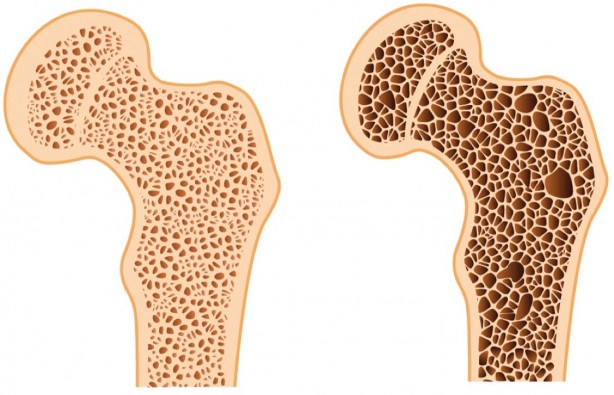

Her 3 kadının ve her 5 erkeğin 1’in görülüyor Günde sadece yarım saat ile kurtulabilirsiniz

Osteoporozu önlemenin mümkün olduğunu belirten Fizik Tedavi ve Rehabilitasyon Uzm. Dr. Öğr. Üyesi Elif Berber, “Osteoporoz önlemenin en önemli yolları D vitamini kullanmak, güneşlenmek ve kemiği güçlendirici egzersizleri uygulamaktan geçer. Yarım saatlik tempolu yürüyüşler şiddetle tavsiye edilir” dedi.